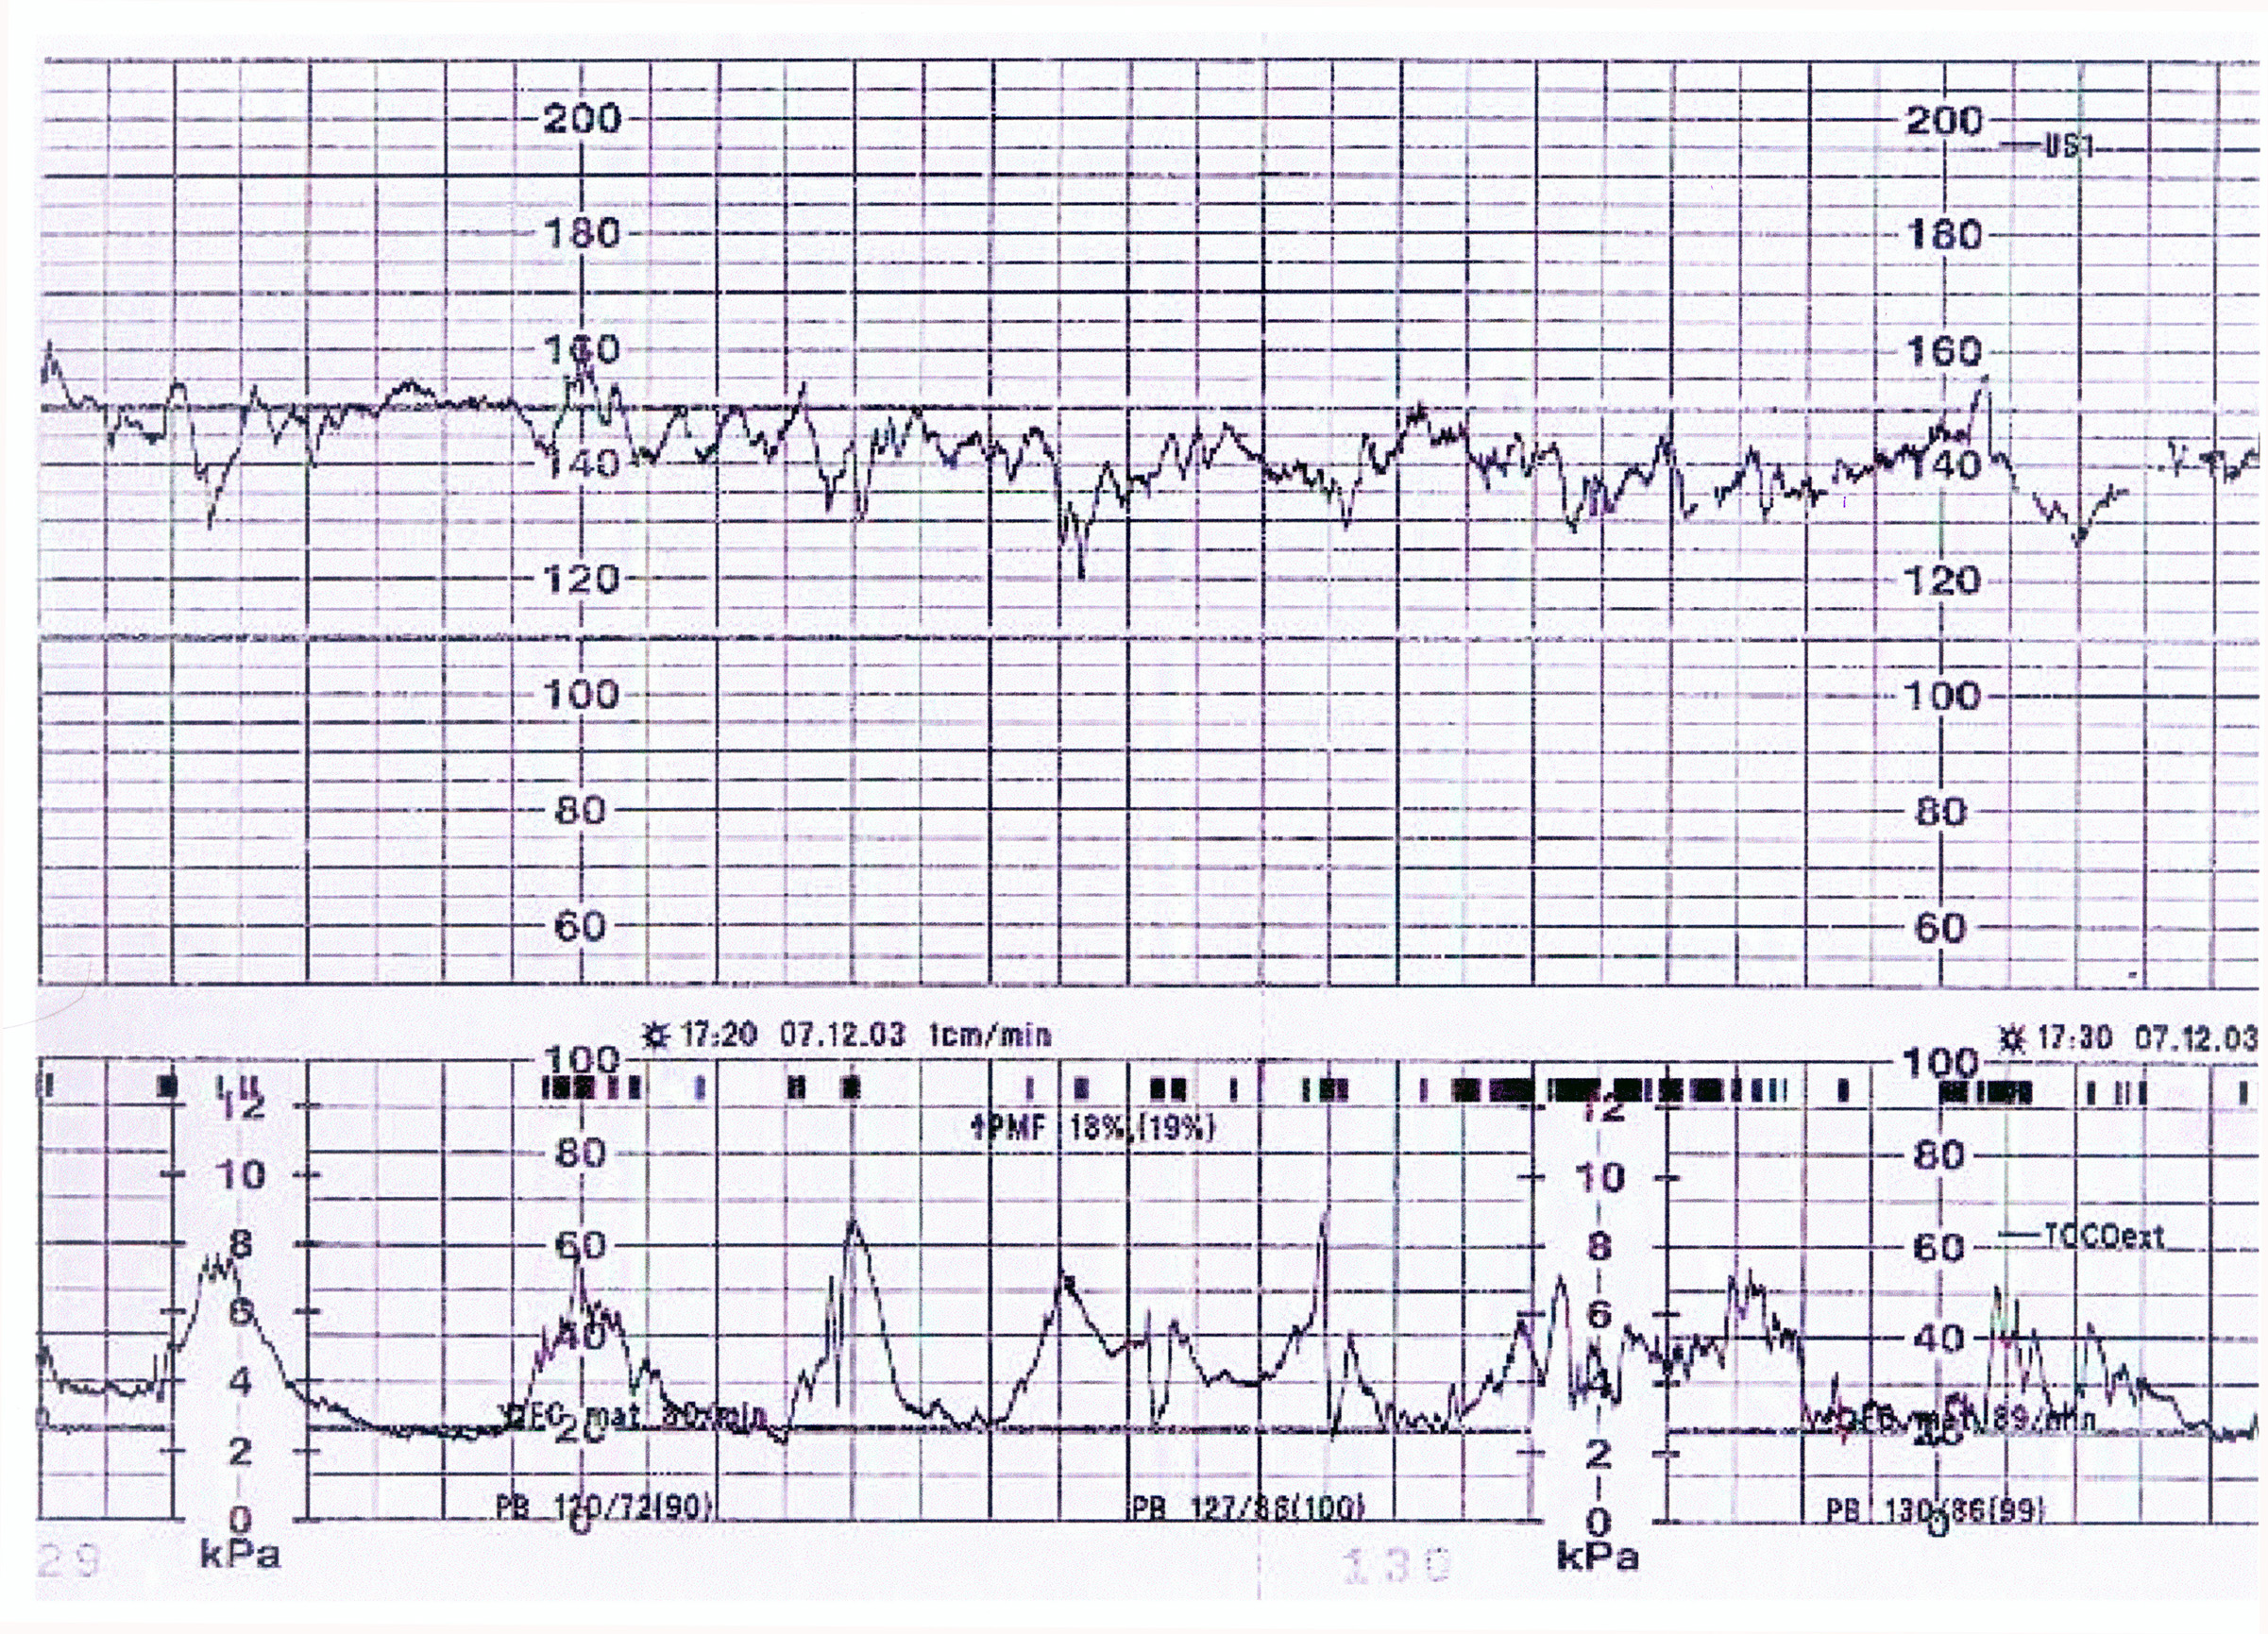

Vous

décidez de réaliser aussitôt un monitoring foetal

dont voici le début du

tracé.

Dans quel but ? Quelles informations obtenez-vous de ce monitoring ?